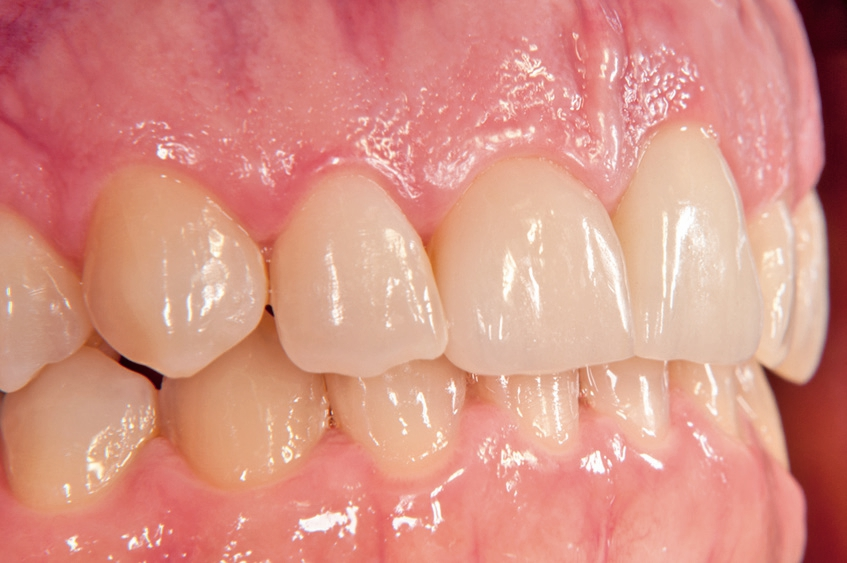

Gleichzeitig mit der prothetischen Versorgung des Implantats wurde auch für Zahn 11 ein Veneer geplant. Zum Einsatz kam ein Zeramex T Implantat Durchmesser 5,5 mm, Länge 12 mm. Für die Kronenversorgung wurde ein mit e. Max überpresstes CAD-Abutment gewählt. Während der Einheilphase des Implantats kam eine Sunflex-Prothese zum Einsatz.